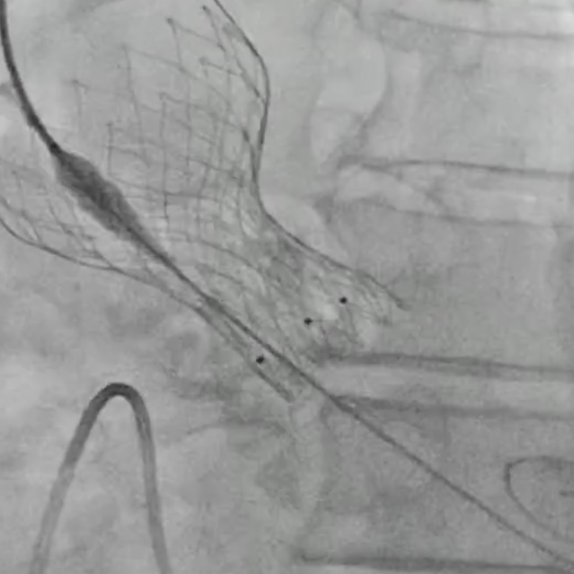

瓣膜过弓

瓣膜释放

超声引导确认植入深度

回收后再次释放, 瓣膜植入同轴性良好,展开充分,反流消失, 手术顺利完成